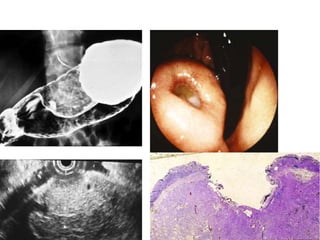

• Linitis plastica

appearance caused by

eosinophilic

gastroenteritis.

• The clue to the

diagnosis relates to the